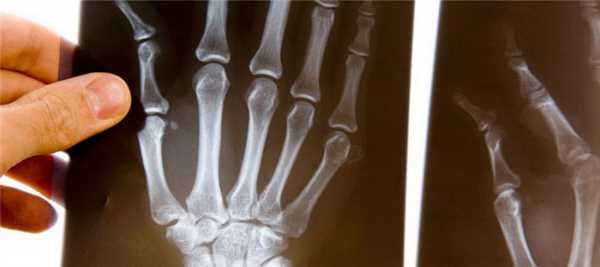

- рентген стоп и кистей, КТ, МРТ, а также УЗИ других органов;